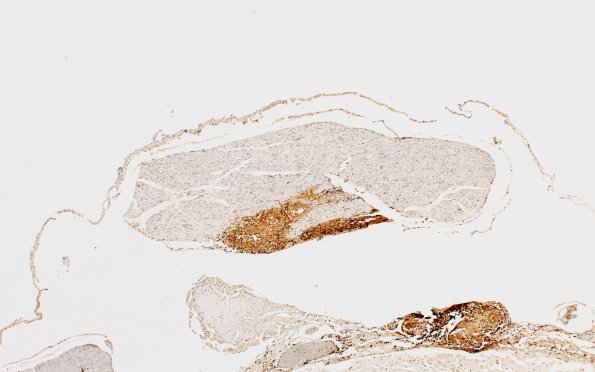

4C2 Neurosarcoid NP (Case 4) CD45 4X

4C2,3 The root identified by an arrow in image 4B1 stained with CD45 to demonstrate the granuloma. (CD45 IHC)-